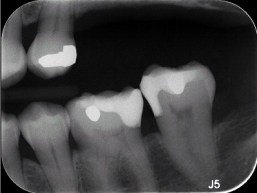

#20 DO

#19 DO and #18 MO